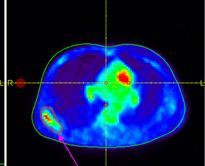

Chúng tôi đã tiến hành ghi hình PET/CT toàn thân cho bệnh nhân và dùng hình ảnh PET/CT để lập kế hoạch xạ trị cho bệnh nhân.

Trên hình ảnh CT rất khó để nhận diện tổn thương di căn xương bả vai phải, một số cung xương sườn của bệnh nhân cũng như tổn thương di căn cột sống. Tuy nhiên với việc kết hợp hình ảnh PET và CT, việc đánh giá tổn thương di căn xương để tiến hành lập kế hoạch xạ trị trở nên chính xác hơn nhiều.

Một ưu điểm vượt trội của PET/CT so với các phương thức chẩn đoán hình ảnh hiện nay là kết hợp được cả thông tin chuyển hóa (metabolic) hay thông tin chức năng (functional) của PET với thông tin cấu trúc giải phẫu của CT. Kết quả là mang lại hình dung chính xác nhất về khối u, đặc biệt là những vùng khối u có khả năng đang hoạt động (đang có khả năng phát triển, xâm lấn và di căn…). Sau các phương pháp điều trị, tổ chức ung thư có thể chưa thay đổi về mặt kích thước trên hình ảnh CT nhưng đã thay đổi bản chất đáng kể trên PET. PET/CT giúp chúng ta tập trung điều trị các vùng khối u còn hoạt động, đảm bảo điều trị đúng và đủ, tránh được những điều trị không cần thiết, mang lại kết quả điều trị cao hơn, giảm bớt các biến chứng, kéo dài thời gian sống thêm và nâng cao chất lượng cuộc sống.